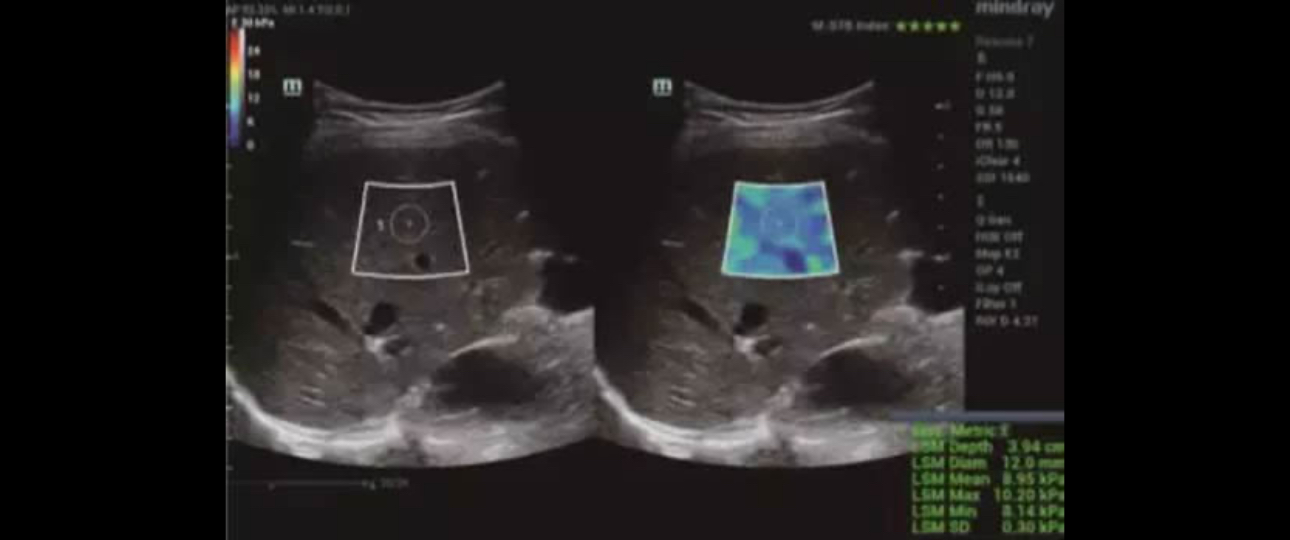

Applying with the Sound Touch Elastography, the system showed a median value of 8.83 kPa (IQR/M = 1.8%) which indicated significant fibrosis. The liver stiffness measurement was also reliable.

Transient elastography with a FibroScan device was performed in the same session soon after the evaluation with the Resona 7 and the values obtained was 8.5 kPa. Liver biopsy, performed a week later, showed stage 2 fibrosis.[3]

With availability of an ultrasound system, in which shear wave elastography technique is implemented, experts were able to evaluate the liver stiffness whose results were compatible with significant fibrosis (F2), confirmed by liver biopsy later.

As the case implied, STE can significantly increase the odds of early detection by creating a safe ultrasonic shear wave to disturb soft tissue as it penetrates through the tissue. The ultrasound system can then analyze and evaluate tissue stiffness within a selected region in the scanning area.

After that, it will interpret and display real-time information in a color-coded image based on the softness and stiffness of the tissue which help to indicate what kind of anomaly is present.

In addition, STE provides a motion stability index and reliability chart to help ensure accuracy and reproducibility of the examination.

In a nutshell, integrated with MindrayŌĆÖs exclusive Ultra-wide Beam Tracking technology, STE demonstrates a giant leap on ultrasound performance, mainly manifesting in better penetration, more accurate quantification and less acoustic power.